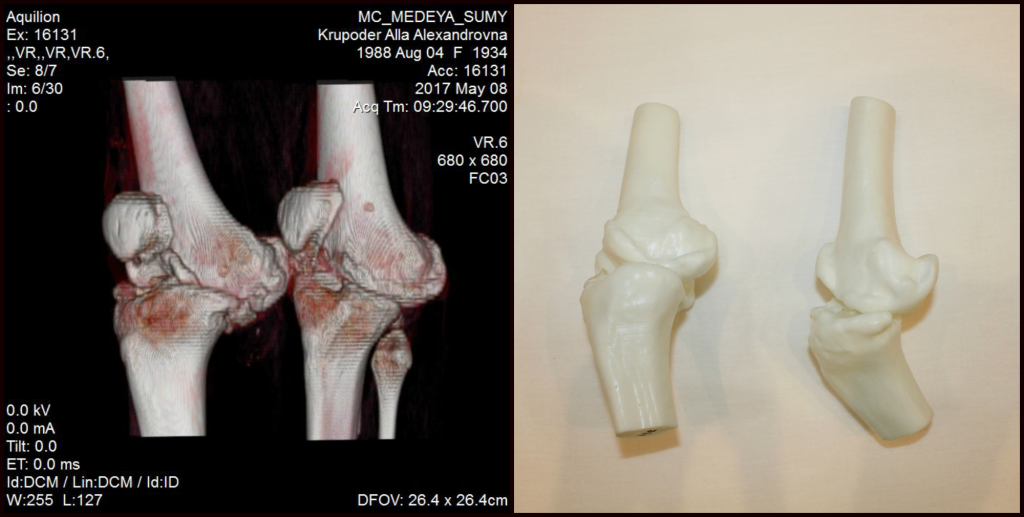

MedinUa первыми в Украине внедрили технологию 3D моделирования кости. Это позволяет нашим хирургам уже до операции знать место разреза, подготовить нужные инструменты для оперирования и даже сделать пробную операцию. Итак:

• хирург будет полностью знать строение вашей кости;

• операция будет совершена на 45 минут быстрее;

• весь процесс займет в 3 раза меньше времени;

• вероятность благоприятного исхода увеличиться до 93%;

• быстрое выздоровление и недолгий период реабилитации.

Как делятся с нами наши пациенты – возможность 3D моделирования в MedinUa, делает их ещё более уверенными в результате, и дает им гарантию в доверии своего здоровье нашей клинике. Такие отзывы очень вдохновляют нашу команду, и мы готовы все больше и больше расширять свой функционал до новых масштабов украинской медицины.